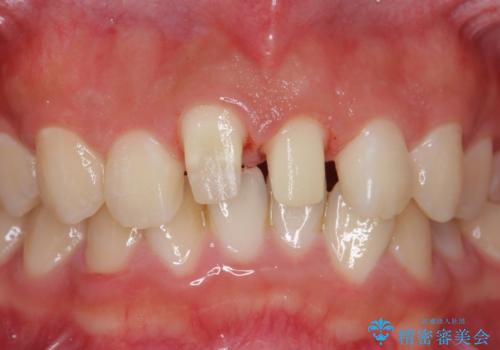

- 前歯の突出を主訴に来院。

矯正治療は絶対したくないとのことでした。

矯正治療をするメリット(神経を取らずに済む、歯を削らずに済む、セラミックを入れずに済む、歯ぐきのラインが整う)をお話しましたが、希望されませんでした。

部分矯正なども提示しましたが、早く治すセラミック治療を選択されました。

前歯の角度や歯ぐきのラインに差が大きかったため、やむなく神経をとり、歯ぐきの手術を行い出来るだけ歯ぐきのラインを整えるようにしました。

手術をしなければ左上1番の歯ぐきのラインは左上2番よりも下にきてしまい、長さの短い歯になってしまうところでした。